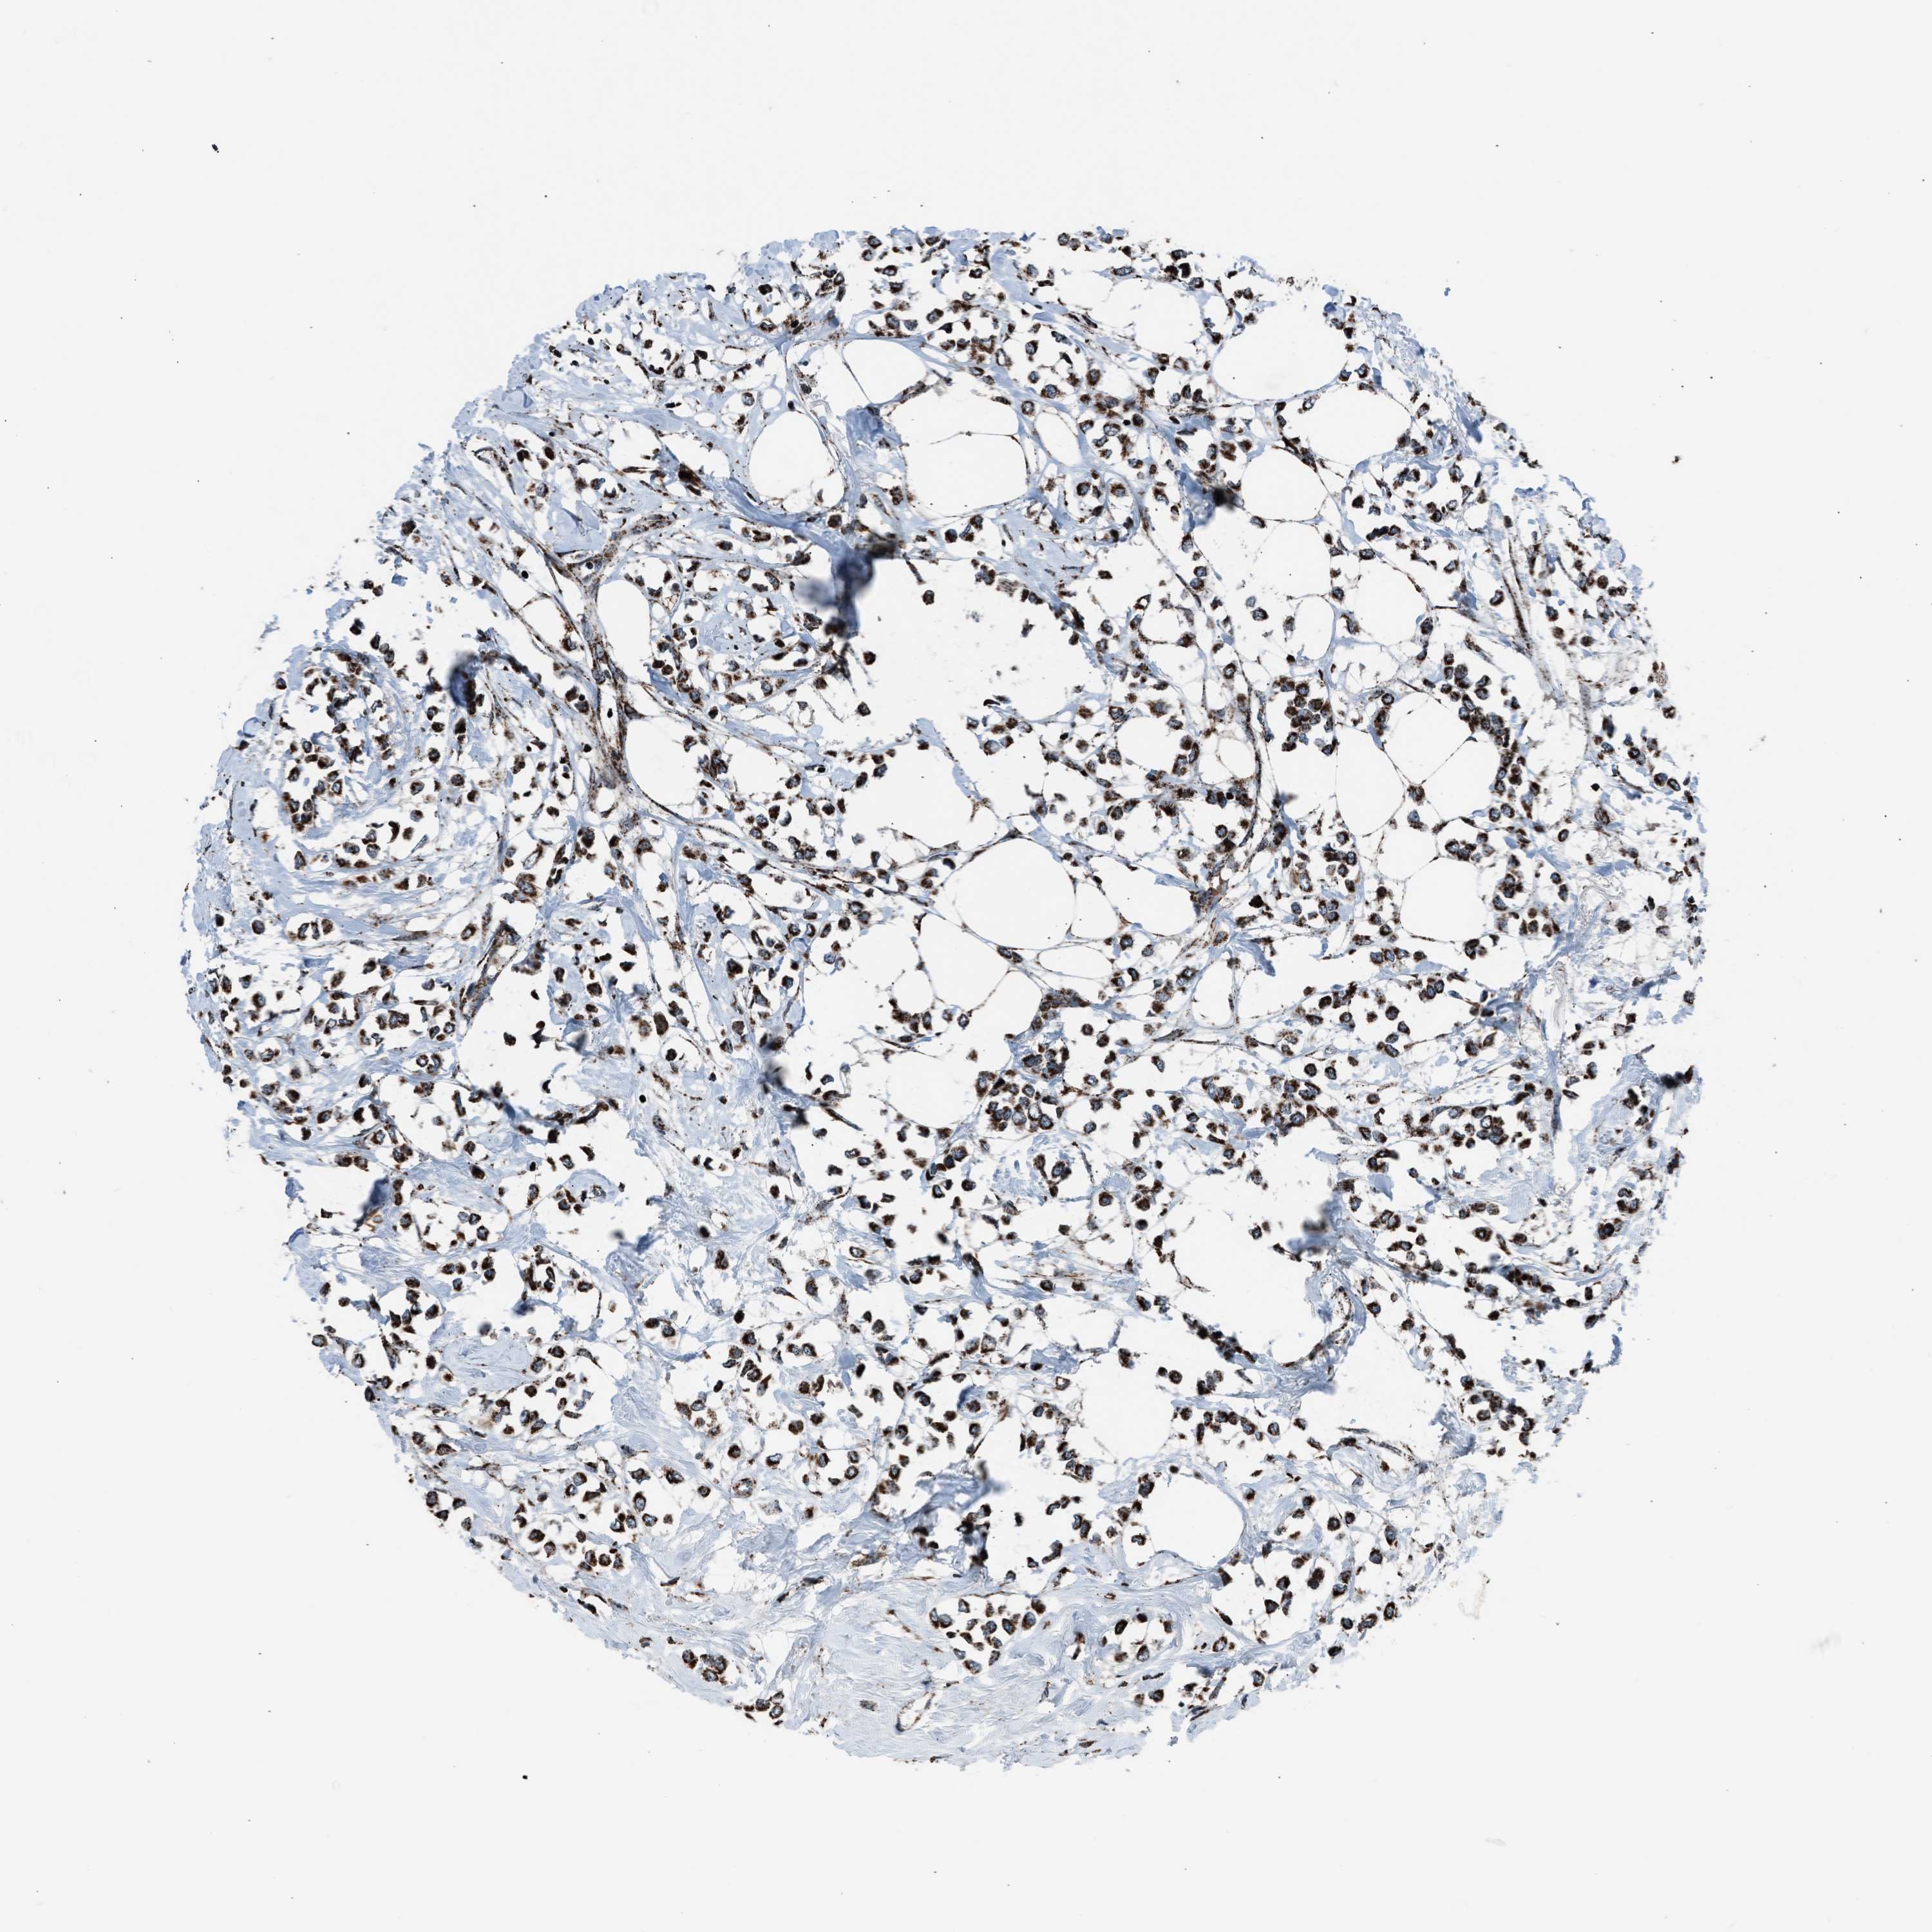

CANCER BREAST CANCER Show tissue menu

BRCA TCGA BRCA VALIDATION PROTEIN EXPRESSION

ANTIBODIES

AND

VALIDATION